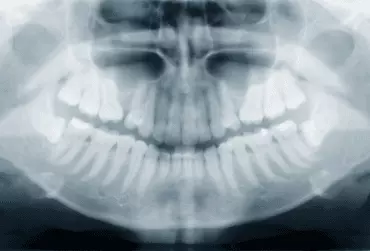

Współczesne wymagania estetyczne pacjentów oraz złożoność przypadków wymagają od  lekarzy coraz częstszej współpracy interdyscyplinarnej. Jednym z takich przykładów jest współpraca pomiędzy implantologiem a ortodontą.